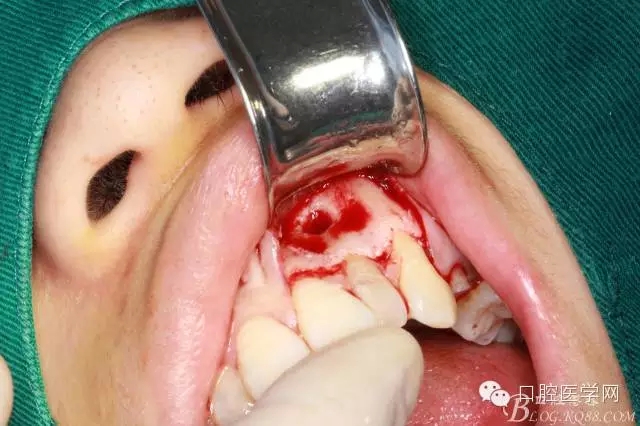

翻全厚瓣(-)

翻全厚瓣(二)

翻全厚瓣后暴露骨面

確定根長(根管充填時已確定)

去 骨

可見囊腫

刮凈囊腫